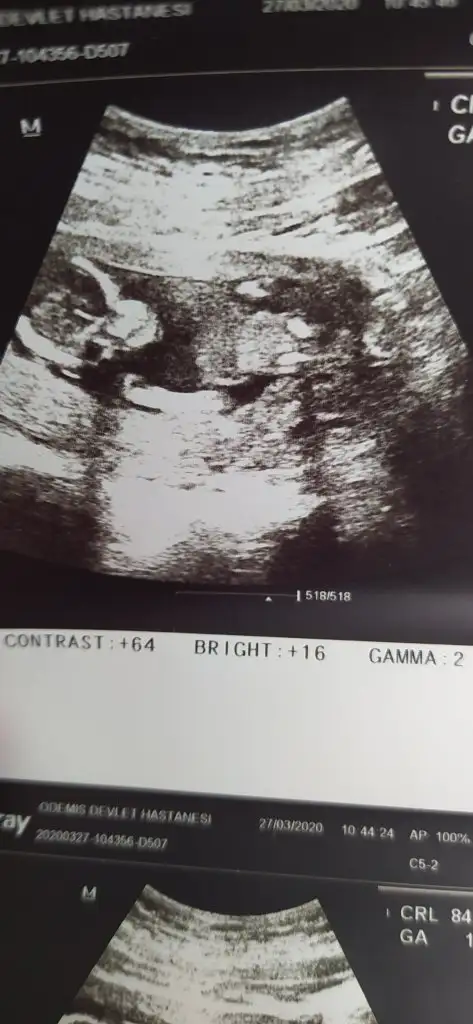

12+1 doktor bi tahminde bulundu ama değişebilir dedi.

Nubu ne dik nede paralel karşıya bakıyor önceki yorumum kız yönündeydi sanki bu defa kız gibi diyecem ama nubu yanıtıyor şu an başka usg varmı